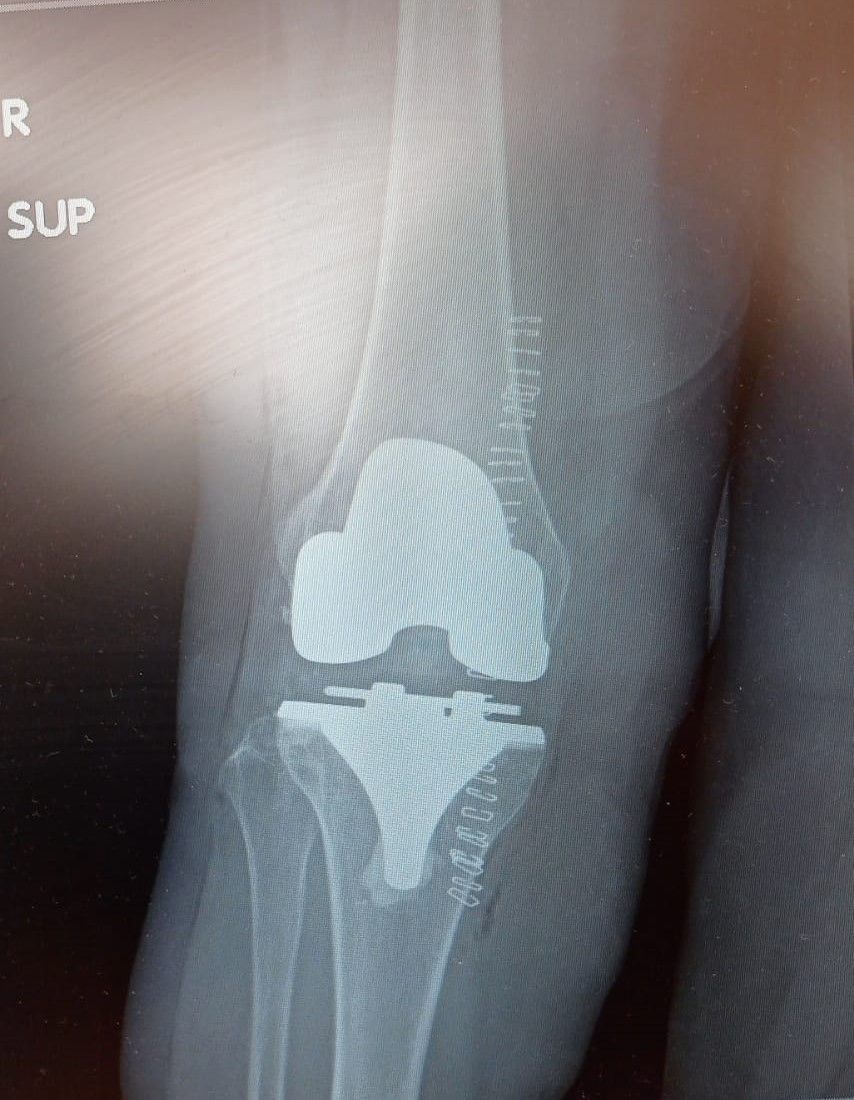

La protesi di ginocchio è costituita da una componente tibiale, una femorale, entrambe in lega di cromo-cobalto, ed un inserto in polietilene che aumenta la congruenza articolare e la stabilità dell’impianto protesico. In genere, le componenti protesiche si fissano all’osso con il cemento, oppure utilizzando degli impianti in tantalio, materiale che si osteointegra completamente entro 3 mesi, senza necessità di cementare.